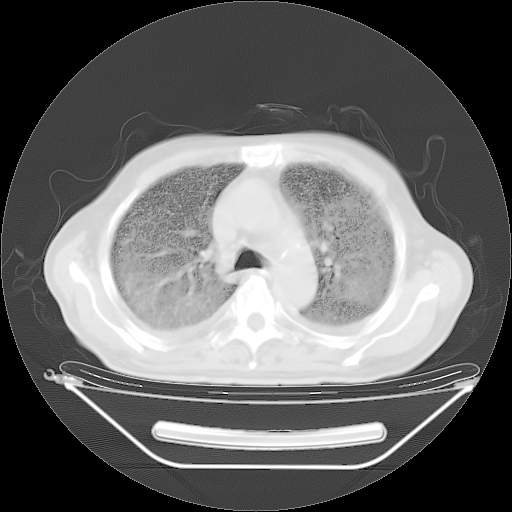

今天复查肺部CT,发现双肺广泛磨玻璃样改变。所以我把3月19日和5月9日相隔50天的肺部CT上传。请大家会诊。

5月9日肺部CT(在4月27日齐鲁医院肺部CT描述部分肺组织磨玻璃样改变,12天后肺组织广泛磨玻璃样改变)

大致读了系列胸部CT:纵隔窗无明显异常,肺窗:从4、27至今:主要是双肺中下野外带可见毛玻璃样改变,目前处于急性肺泡炎阶段,至于原因考虑1、结替组织或胶原血管性疾病所致?2、恶性疾病如恶组在肺部所致的表现或细支气管肺泡癌?3、药物或其它原因如肺蛋白沉着症所致肺泡炎目前不太可能?总之,明天就去请我院的呼吸科、感染科、血液科和临免专家会诊哈。